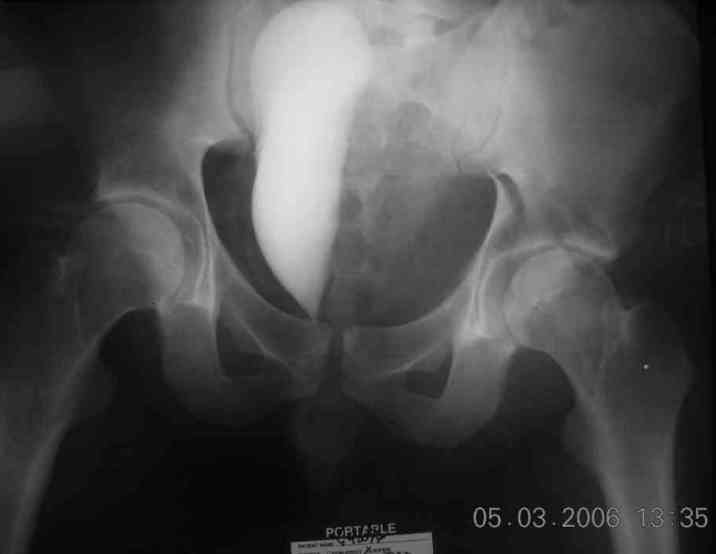

45 yo male in MVA, only other injury=small subarrachnoid bleed (neurologically fine, GCS never <14), with this transverse & associated posterior wall fx-dislocation 7/7

In skeletal traction thru distal femoral pin 40 lbs with decent reduction - except for the free fragments in the hip joint. ORIF planned for post-injury day 11.

Stabilize anterior column with fluoroscopically guided screw across this end of the transverse fx - As usual, after your reduction of the femoral head, the transverse fx became minimally displaced - slightly gapped without stepoff. I usually (reduce &) stabilize the medial side of the posterior column (transverse fx) with a short plate - before placing the anterior screw unless the transverse fx is undisplaced.

Biggest problem appears to be impaction & comminution of the posterior wall fx site - you've left out some CT cuts. This is not just fragments in joint. It may leave a deficient area, &/or block satisfactory posterior wall reduction.